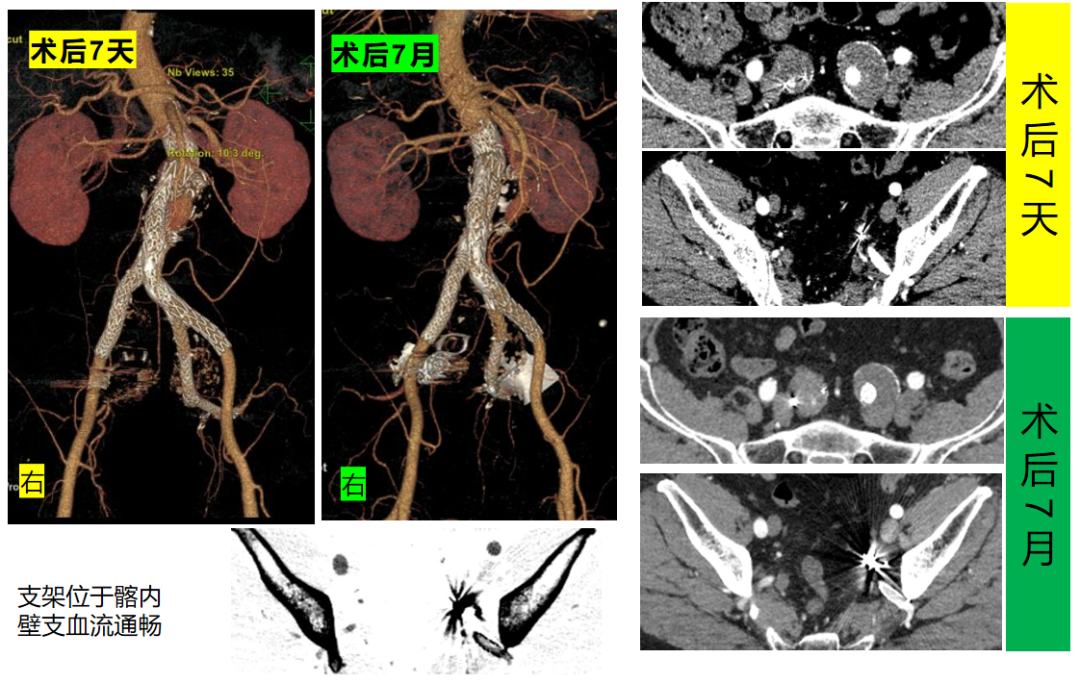

术后随访

术后7天CTA显示支架位于髂内动脉分支内,血流通畅,无内漏等并发症迹象,周围组织未见异常。术后7月CTA检查,支架持续保持良好位置,髂内动脉分支血运稳定,动脉瘤无复发及增大,血管周围组织状态正常,表明手术远期效果良好。